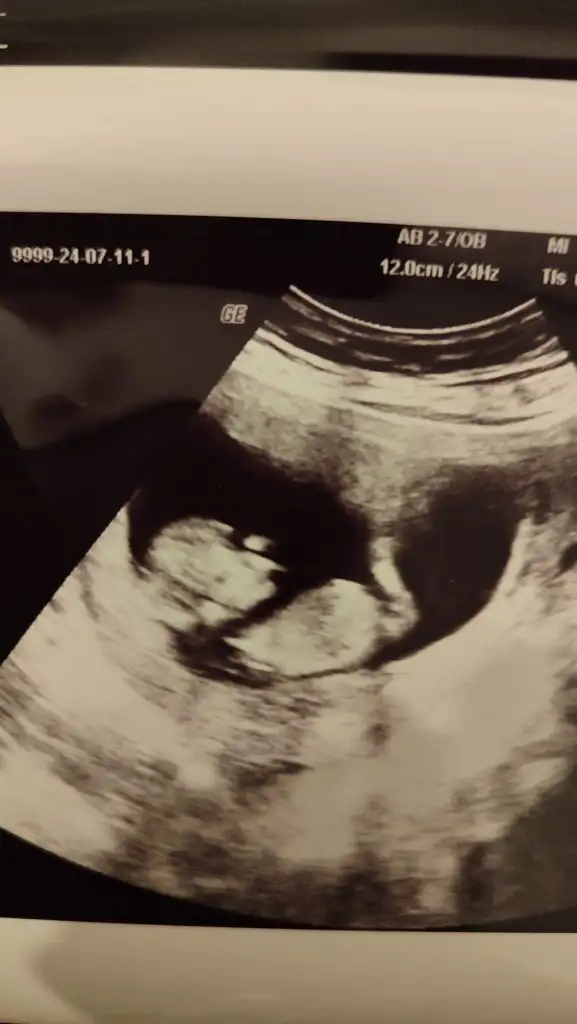

Merhaba 8 haftalık karından ultrason tahmini olan varmıdır?

• IMG_2160.webp

IMG_2160.webp

47,7 KB · Görüntüleme: 95